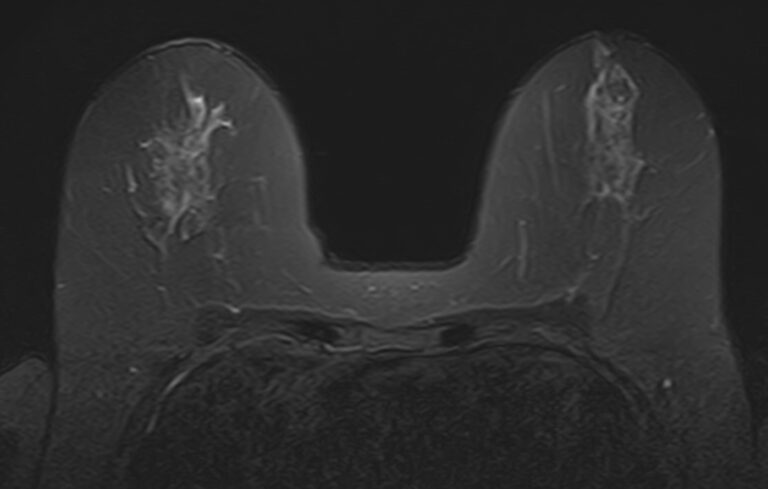

Использование контраста позволяет выявлять опухоли малых размеров, дает важную информацию о локализации опухоли, как она связана с окружающими тканями и насколько развита ее система кровоснабжения.

- Уточнение патологии, найденной при стандартной маммографии или УЗИ молочных желез;